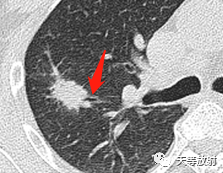

27c1b637ca1e79bb0691e64b16e95d9b.png

这个层面出现囊腔+实性结节,囊壁较厚。

实性结节呈分叶状改变,邻近胸膜增厚,有牵拉改变,凹陷征。